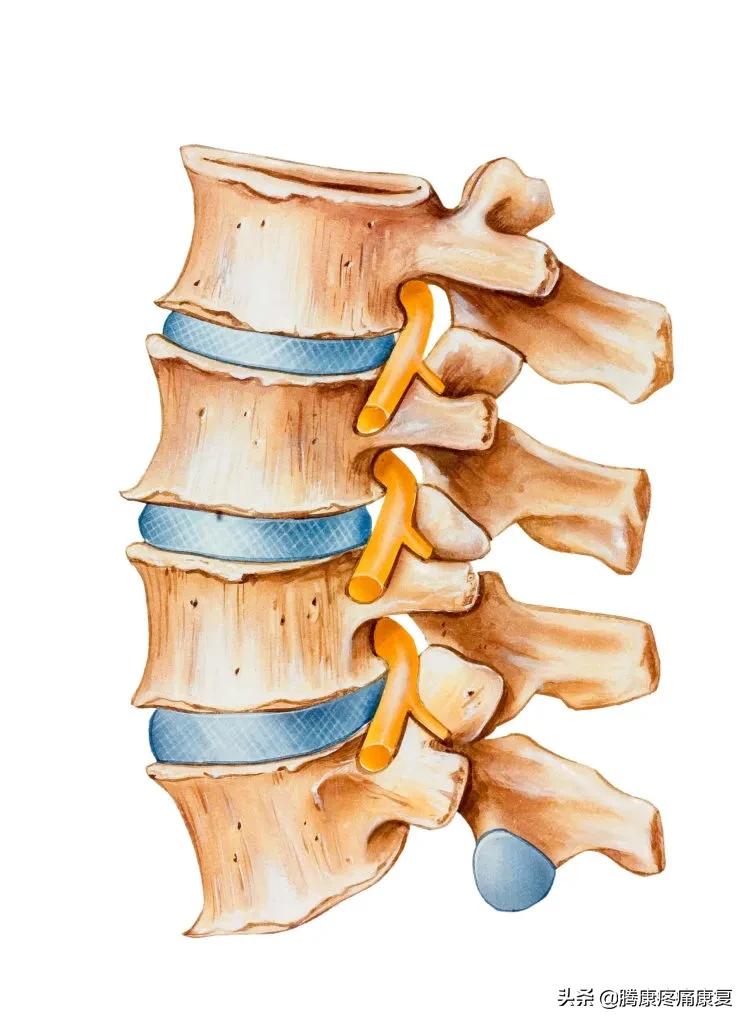

人体脊柱在各个节段是含有特定生理曲线的。这些曲线要么向内(朝向身体前部),要么向外(朝向身体后部),呈交替模式,形成“s”形。颈部和腰部的椎骨略微向内弯曲,中部和胸部略微向外弯曲。这些曲线帮助我们在静止和运动时保持正确的姿势和平衡。

平背表明脊柱失去了正常的生理曲线,正常情况下当我们从侧面观察身体时,矢状轴与垂直方向的对齐不应该超过5MM,而平背综合征的患者,由于重心前移,轴心距垂直距离会超过5MM。